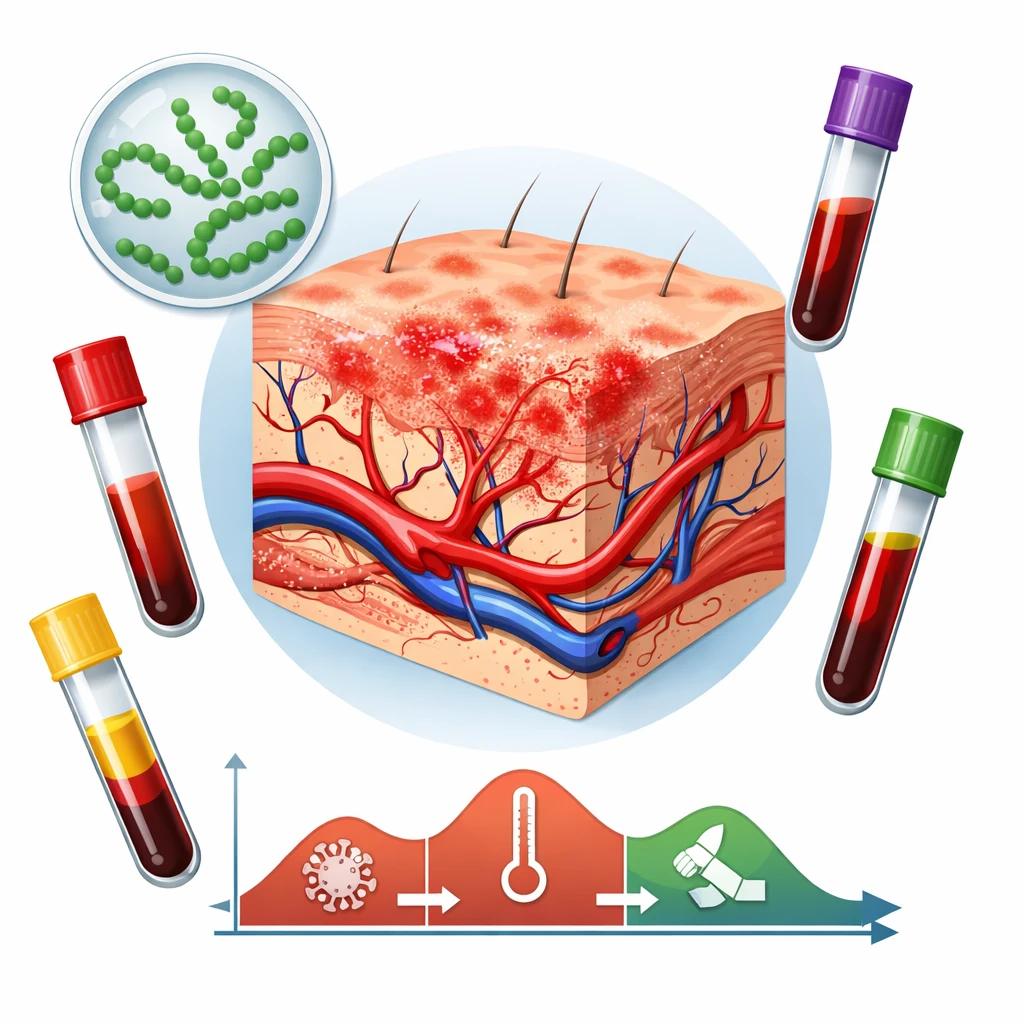

شواهد بالینی و آزمایشگاهی نشان دادهاند که کمبود ویتامین D با مسیرهای زیر خطر نوروتوکسیسیتی را تقویت میکند:

– اختلال در تنظیم کلسیم داخل سلولی: در حضور سموم مانند سرب و جیوه، نبود ویتامین D باعث افزایش ورود کلسیم به سلولهای عصبی و مرگ نورونی میشود.

– کاهش فعالیت گلوتاتیون (GSH): سطح پایین ویتامین D تولید آنتیاکسیدان اصلی مغز را کاهش داده و سلولها را در برابر پراکسیداسیون چربیها آسیبپذیر میکند.

– تقویت التهاب میکروگلیال: کمبود ویتامین D منجر به فعالسازی میکروگلیا و آزادسازی سیتوکاینهای التهابی (IL‑۶، TNF‑α) میشود که اثر سموم را چندبرابر میکند.

– تضعیف سد خونی–مغزی (BBB): بررسیها نشان دادهاند که سطح سرمی ویتامین D کمتر از ۲۰ ng/mL با افزایش نفوذ سموم فلزی به مغز همراه است.